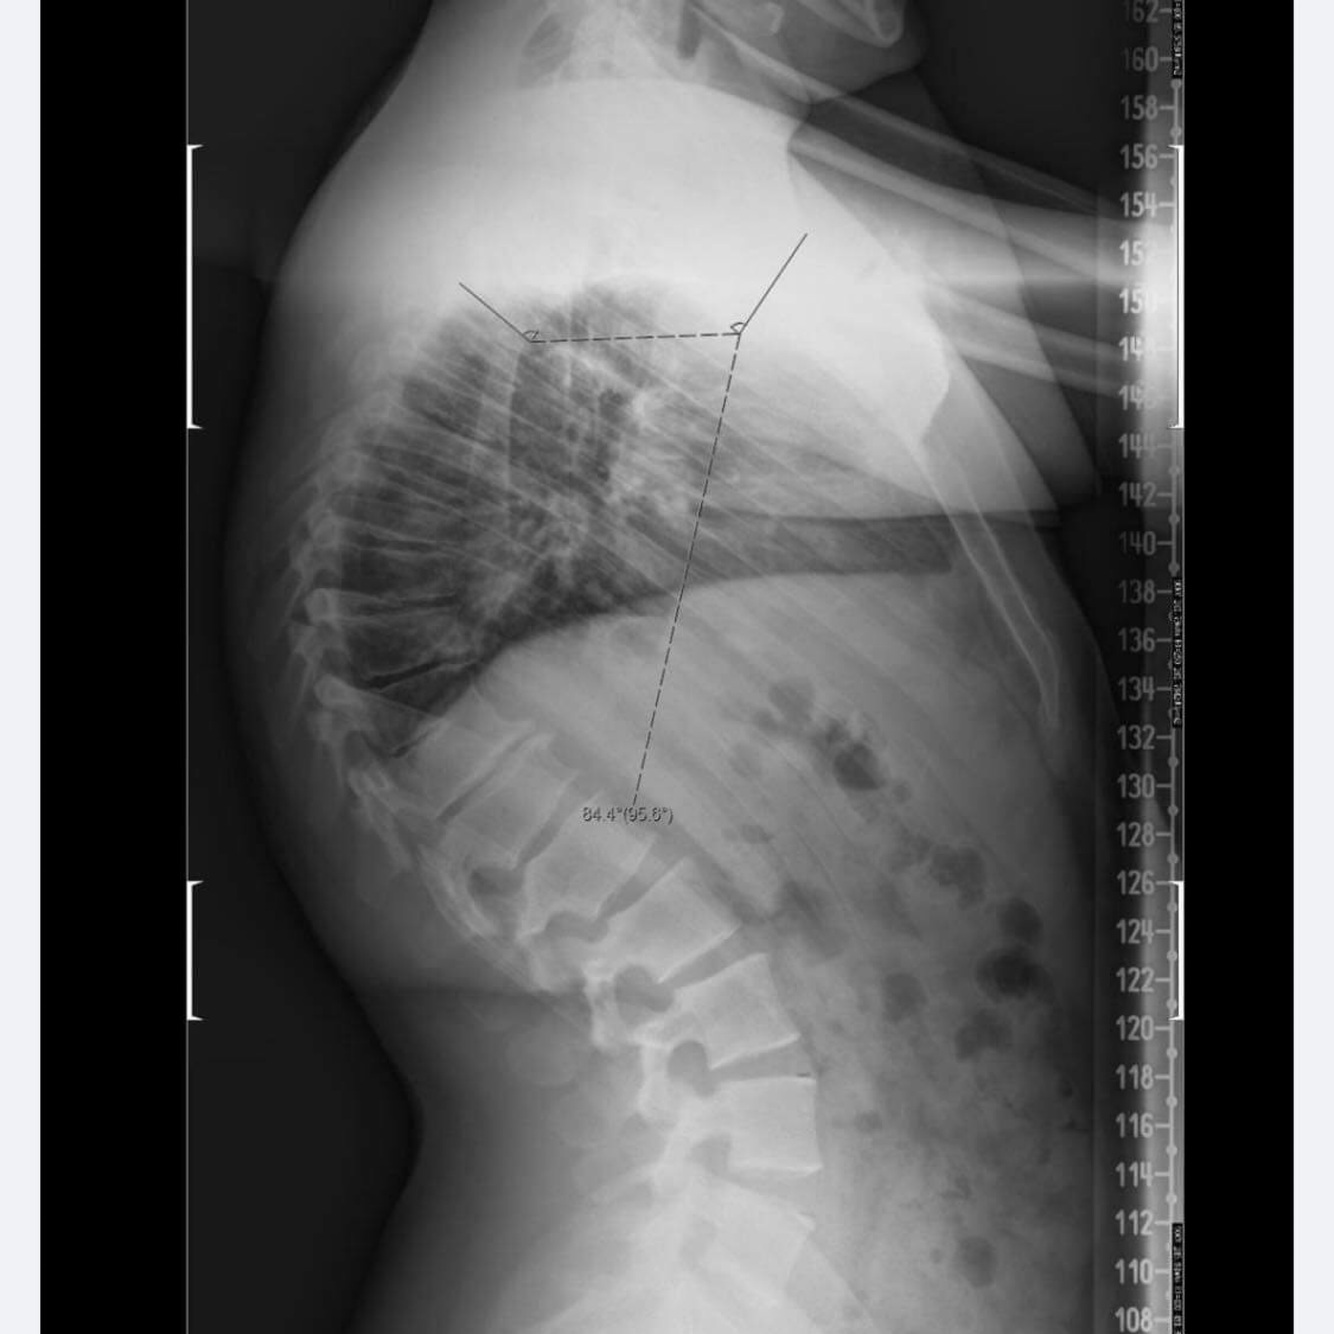

8- Quelle mesure/ligne utile? (Question sur scoliose)

20-21-22: Patient de 20 ans avec douleur thoracique et hypercyphose.

A

Cunieformite

DX: Scheuermann

Approche: Tx chiro

Patient de 20 ans avec douleur thoracique et hypercyphose ( > 50°). Les radiographies démontrent l’apparence cunéiformité des corps vertébraux avec plateaux irréguliers de T6-7-8. Quel est votre plan de traitement ? Référer au médecin de famille Soins conservateur sans ajustement Soins conservateur avec co-gestion médiale Soins multimodal avec ajustement

Soins multimodal avec ajustement